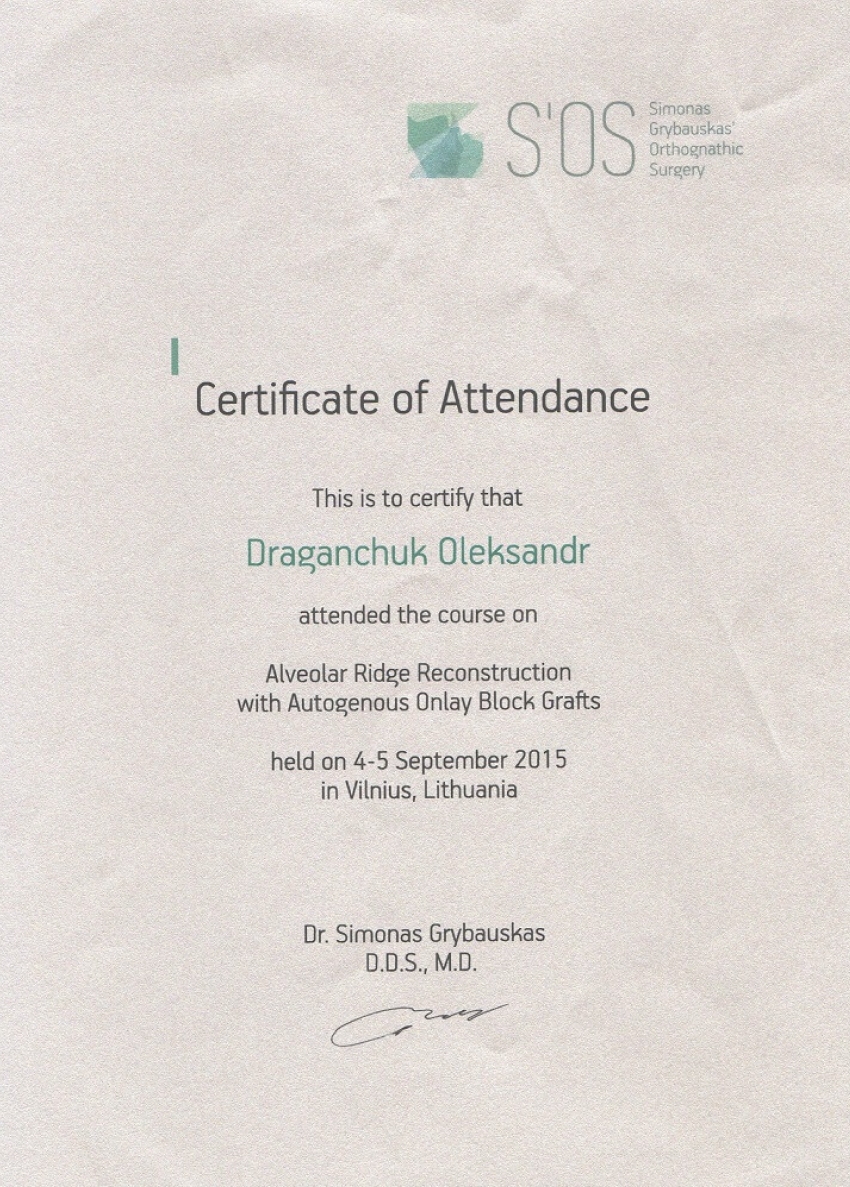

Ми пропонуємо тобі усю стоматологію в одній клініці. У нас ти отримаєш кваліфіковану стоматологічну допомогу: лікування і пломбування зубів та кореневих каналів, послуги з протезування, імплантації та стоматологічної хірургії. Космічна стоматологія Драганчука, це досвідчені фахівці, які навчались та стажувались в Берліні, Парижі, Вільнюсі та Будапешті, найсучасніші та найінноваційніші матеріали та обладнання.